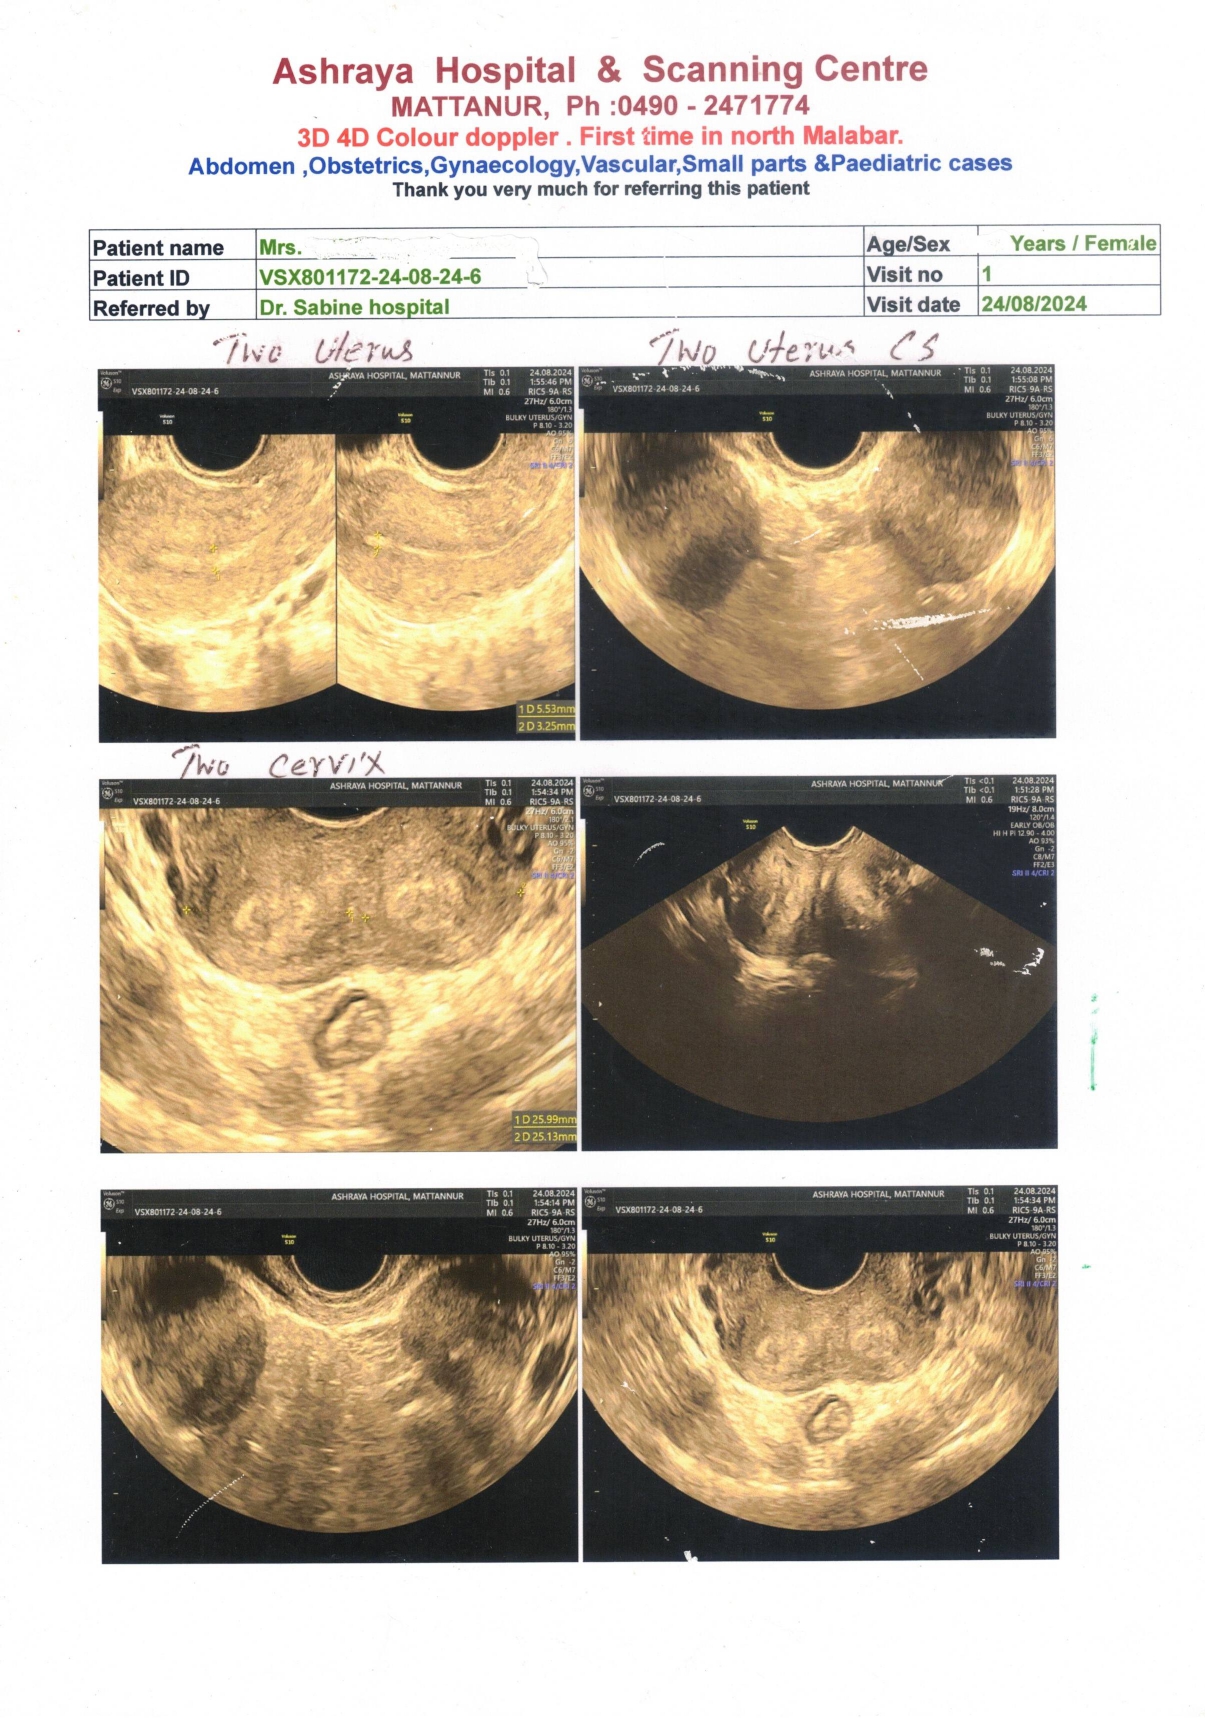

ADVANCED SCANNING REPORT OF TWO UTERUS DONE AT ASHRAYA HOSPITAL